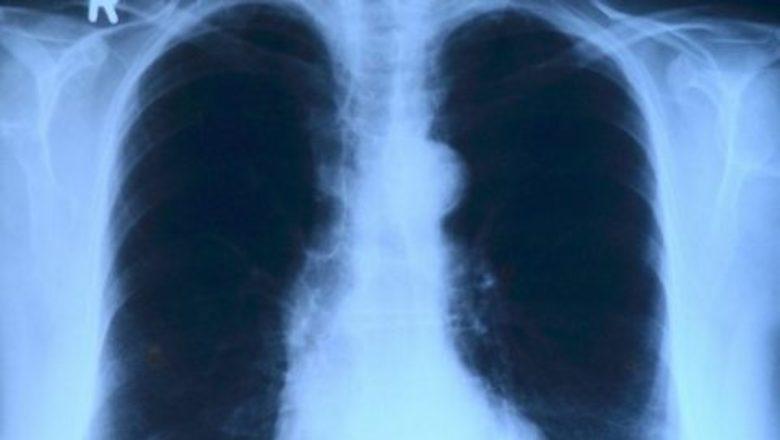

Africa-Press – Mozambique. The number of cases of tuberculosis diagnosed in 2021 in Mozambique has fallen to 98,485, after reaching 115,000 in 2020, the country’s prime minister, Adriano Maleiane, has said.

Maleiane was speaking during the inauguration on Thursday of a centre of excellence dedicated to drug-resistant tuberculosis in Matola, a suburb of Maputo, in a ceremony to mark World Tuberculosis Day, and cited World Health Organisation targets.